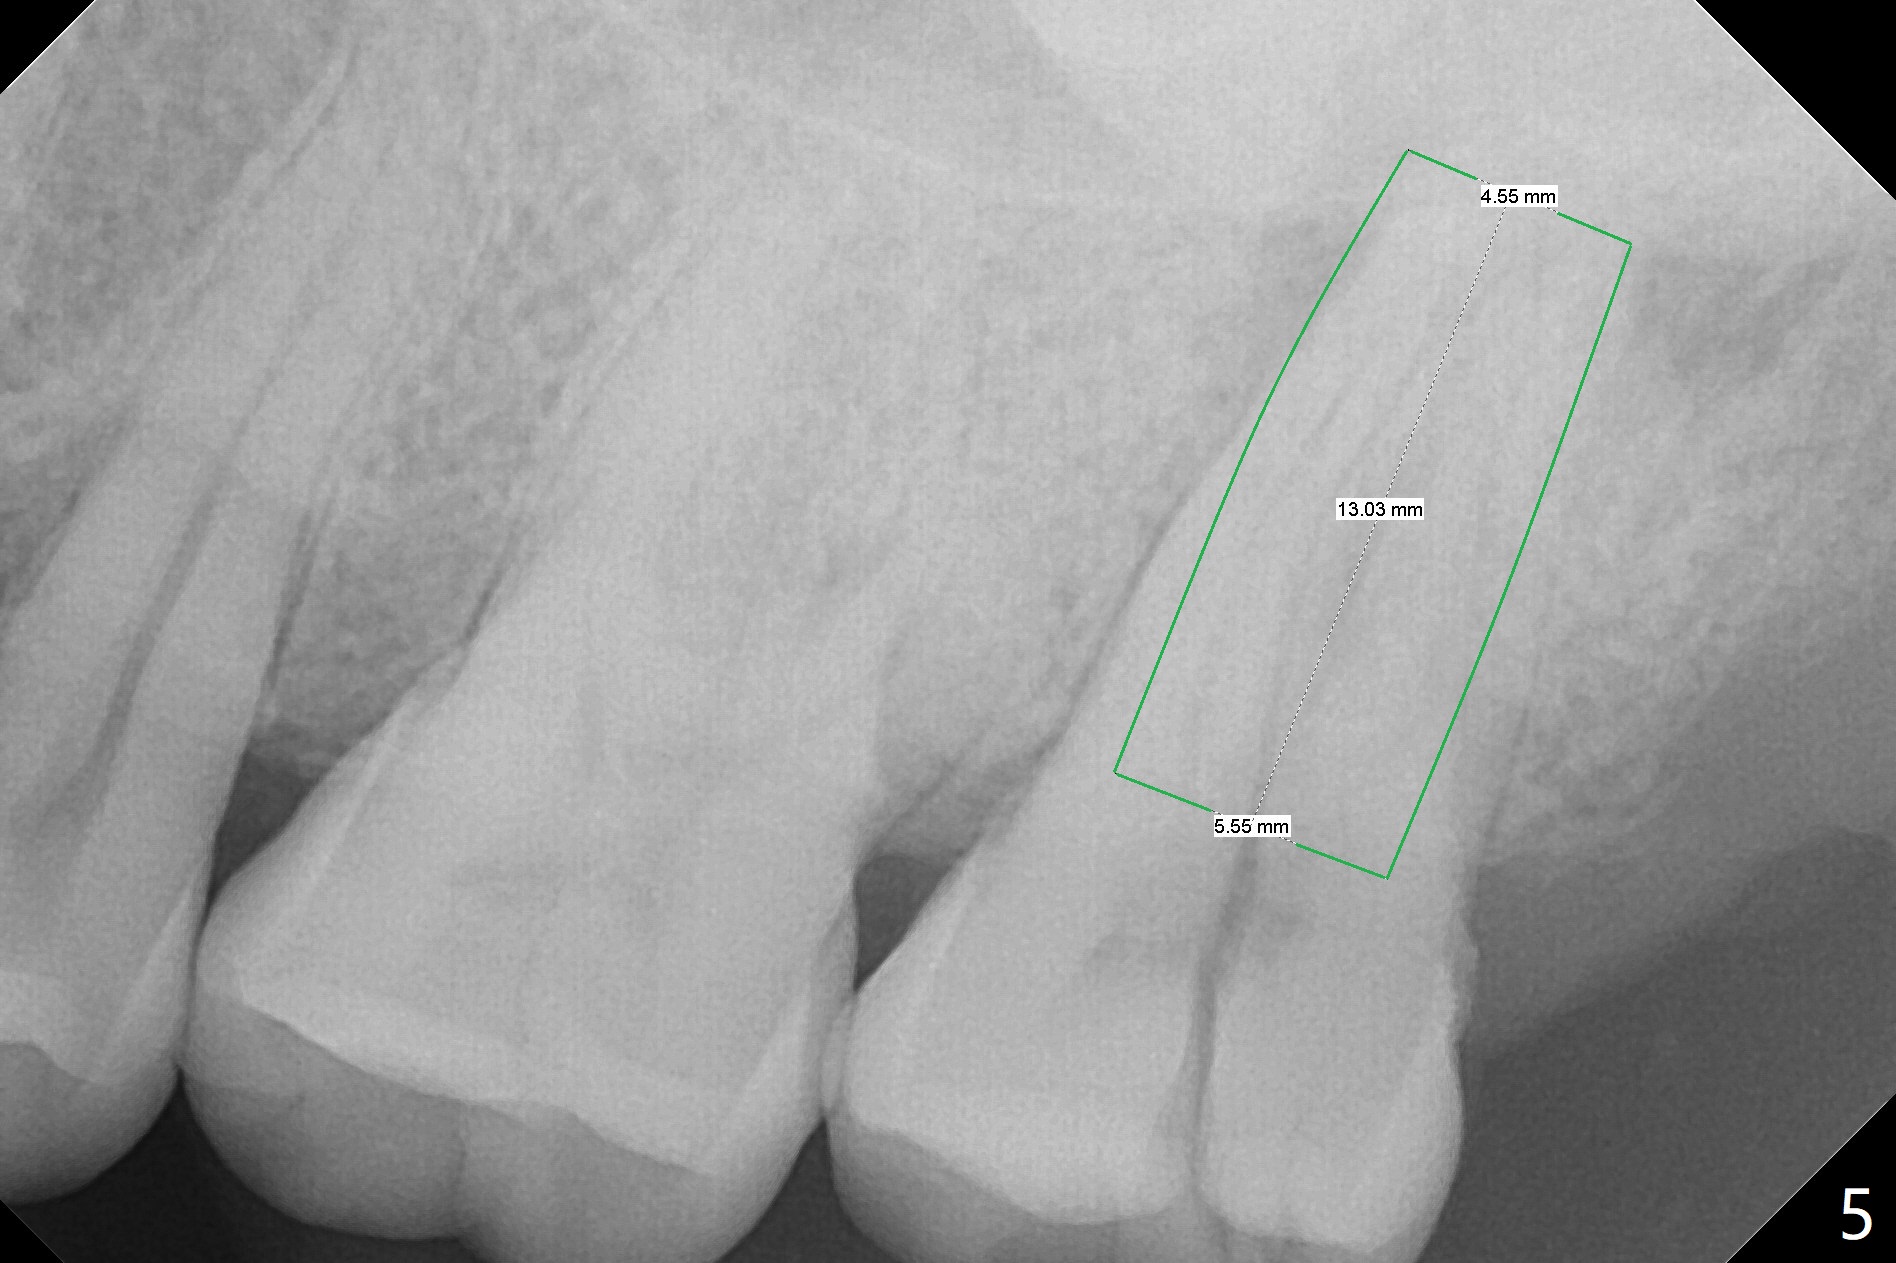

A 44-year-old man presented to clinic with pain of the upper left quadrant (Fig.1), but the affected tooth was not determined until 5 months later (Fig.3,4). Retrospectively the minor crack is visible earlier (Fig.2 arrowheads). It appears that the remaining bone (sinus floor) is limited (Fig.5). Magic Sinus lift or Magic Expanders will be used for sinus lift. Prepare 2-3 pieces of PRF membranes: one or two for sinus lift; the third one to close the socket if primary stability is <30 Ncm.